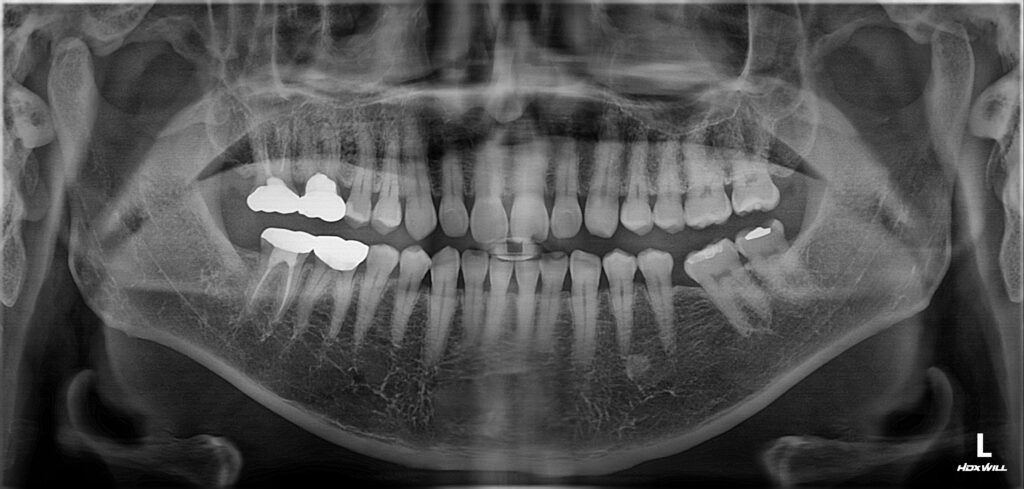

오늘은 광화문치과에서 신경치료를 받은 치아에

염증이 생겨 재근관치료를 진행하신 환자분을

소개해 드리려고 합니다.

환자분께서는 오른쪽 위 크라운을 씌운

어금니에 염증과 통증이 생겨 치아가

흔들리신다며 광화문치과에 내원해 주셨는데요.

오른쪽 위 첫번째 어금니 치아 뿌리 염증으로 인해

잇몸이 부어 고름 주머니가 형성된 것을

확인할 수 있었는데요.

남아 있는 치질의 양이 적고

예후가 좋지 않을 수 있지만

임플란트 식립을 염두에 두고

기존의 크라운을 제거해보기로 하였습니다.